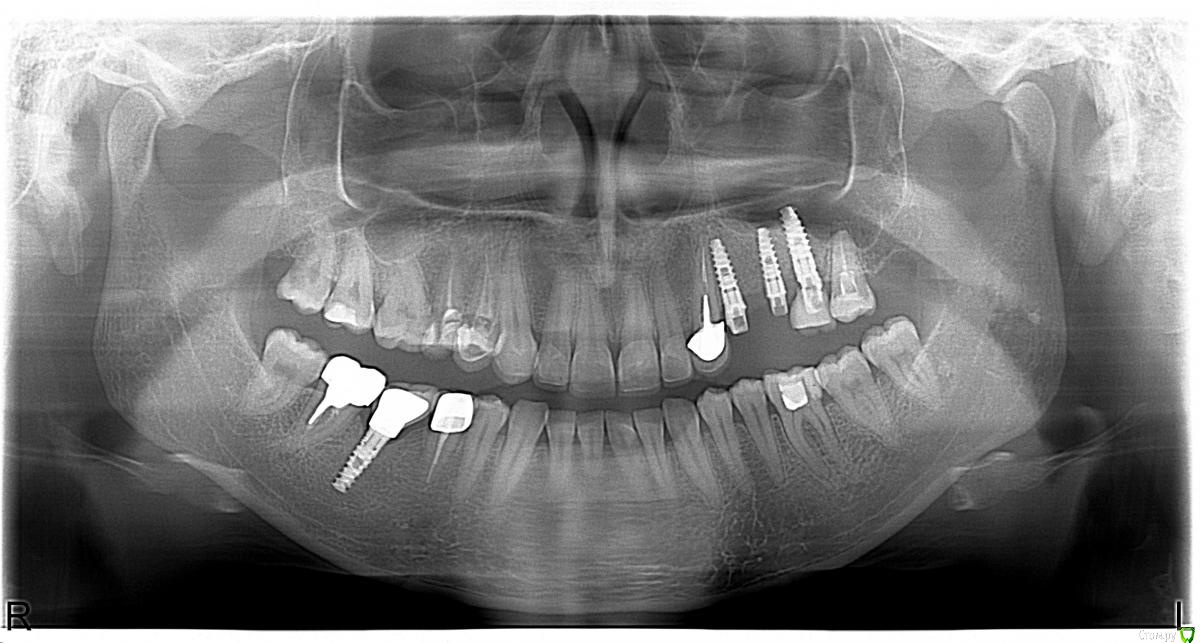

irada Опубликовано 17 декабря, 2019 Поделиться Опубликовано 17 декабря, 2019 Добрый вечер. У меня критическая ситуация. Месяц назад попопала в скорую с температурой и головной болью,выделения из носа не очень обильные но резккий запах, выяснилось -гайморит с левой стороны , сделала курс уколов антибиотиками, но через 2 недели опять поднялась температура и те же самые симптомы , лор отправил делать сникок зубов. У меня как раз с левой стороны подряд 3 импланта сверху , после клыка установлены 3 импланта где жевательные зубы, имланиы были установлены 3 года назад, одновременно с синус лифтингом, врачь говорит что корни имплантов воспалены, вернее кость, там хроническое воспаление, которое вызывает гаймлрит и нужно удалять импланты , чистить, наращивать кость, через время делать новые.Если ли какие то альтернативы? или нет шансов сохранить имплант? Ссылка на комментарий

Bier Опубликовано 18 декабря, 2019 Поделиться Опубликовано 18 декабря, 2019 что-то по этому снимку и кости то вокруг имплантатов не видно, очень плохое качество.Сделайте дентальную компьютерную томографию верхней челюсти, чтобы туда вошли пазухи с соустьями.Но что-то мне подсказывает, что там все на удаление. Ссылка на комментарий

irada Опубликовано 21 декабря, 2019 Автор Поделиться Опубликовано 21 декабря, 2019 вот все что у меня есть, один из снимков сделан после 6 месяцев после имплантацииб там где коронок пока нет. дело в том что я студенка я нахожусь в заграницей и моя кт у врача Ссылка на комментарий

irada Опубликовано 21 декабря, 2019 Автор Поделиться Опубликовано 21 декабря, 2019 что-то по этому снимку и кости то вокруг имплантатов не видно, очень плохое качество.Сделайте дентальную компьютерную томографию верхней челюсти, чтобы туда вошли пазухи с соустьями.Но что-то мне подсказывает, что там все на удаление.мне точно пока не могут сказать нужно ли удалять, сказали может придется как то восстанавливать мембрату потому что имлант пробил синус. и что у меня кость гниет. что надо отрезать кусочек корня импланта восттанавливать мембрану. наращивать кость. но при этом не удалять имплант. я просто первый раз о такой операции слышу Ссылка на комментарий

Bier Опубликовано 24 декабря, 2019 Поделиться Опубликовано 24 декабря, 2019 вот все что у меня есть, один из снимков сделан после 6 месяцев после имплантацииб там где коронок пока нет. дело в том что я студенка я нахожусь в заграницей и моя кт у врачапо этим снимкам криминала нет. Ссылка на комментарий

Bier Опубликовано 24 декабря, 2019 Поделиться Опубликовано 24 декабря, 2019 мне точно пока не могут сказать нужно ли удалять, сказали может придется как то восстанавливать мембрату потому что имлант пробил синус. и что у меня кость гниет. что надо отрезать кусочек корня импланта восттанавливать мембрану. наращивать кость. но при этом не удалять имплант. я просто первый раз о такой операции слышу такую операцию можно сделать. По этому снимку возможно вообще ничего делать не нужно. Нужно посмотреть на КТ. Но повторюсь, ничего криминального нет. Ссылка на комментарий